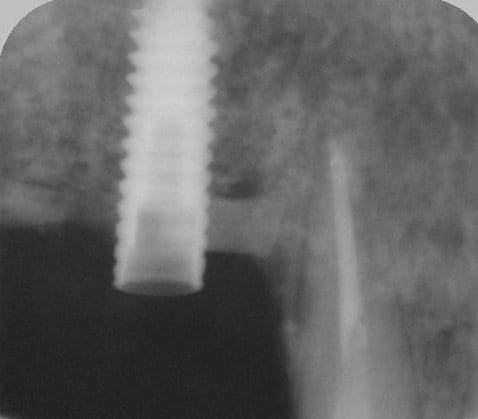

bon et bien ça c'est fait!

curetage (deux bonnes heures) dépose des deux vis d'ostéo et de l'implant en 16, nettoyage implant en 14/15 (axe un peu limite pour cause structure osseuse) et 17.

Vitalos

on croise les doigts.

le greffon placé il y a 6 mois (grosse corticale) était dans le "vide" au niveau de 14, et il m'aurait fallu le piezzo éventuellement (il n'était pas installé, pour cette chir) pour "percer" la corticale sans pression, car à la fraise, je sentais le bloc plier, et nous avons préférés (avec le confrère) tenter un compromis pour la prothèse qui ne sera pas catastrophique et devrait permettre à la patient (qui a déjà subie 2 greffes, menton et ramique, avec un souvenir sympa du menton d'ailleurs)d'avoir une reconstruction fixe.

photos montrant le hiatus greffe/os et pose avec vitalos à la fin